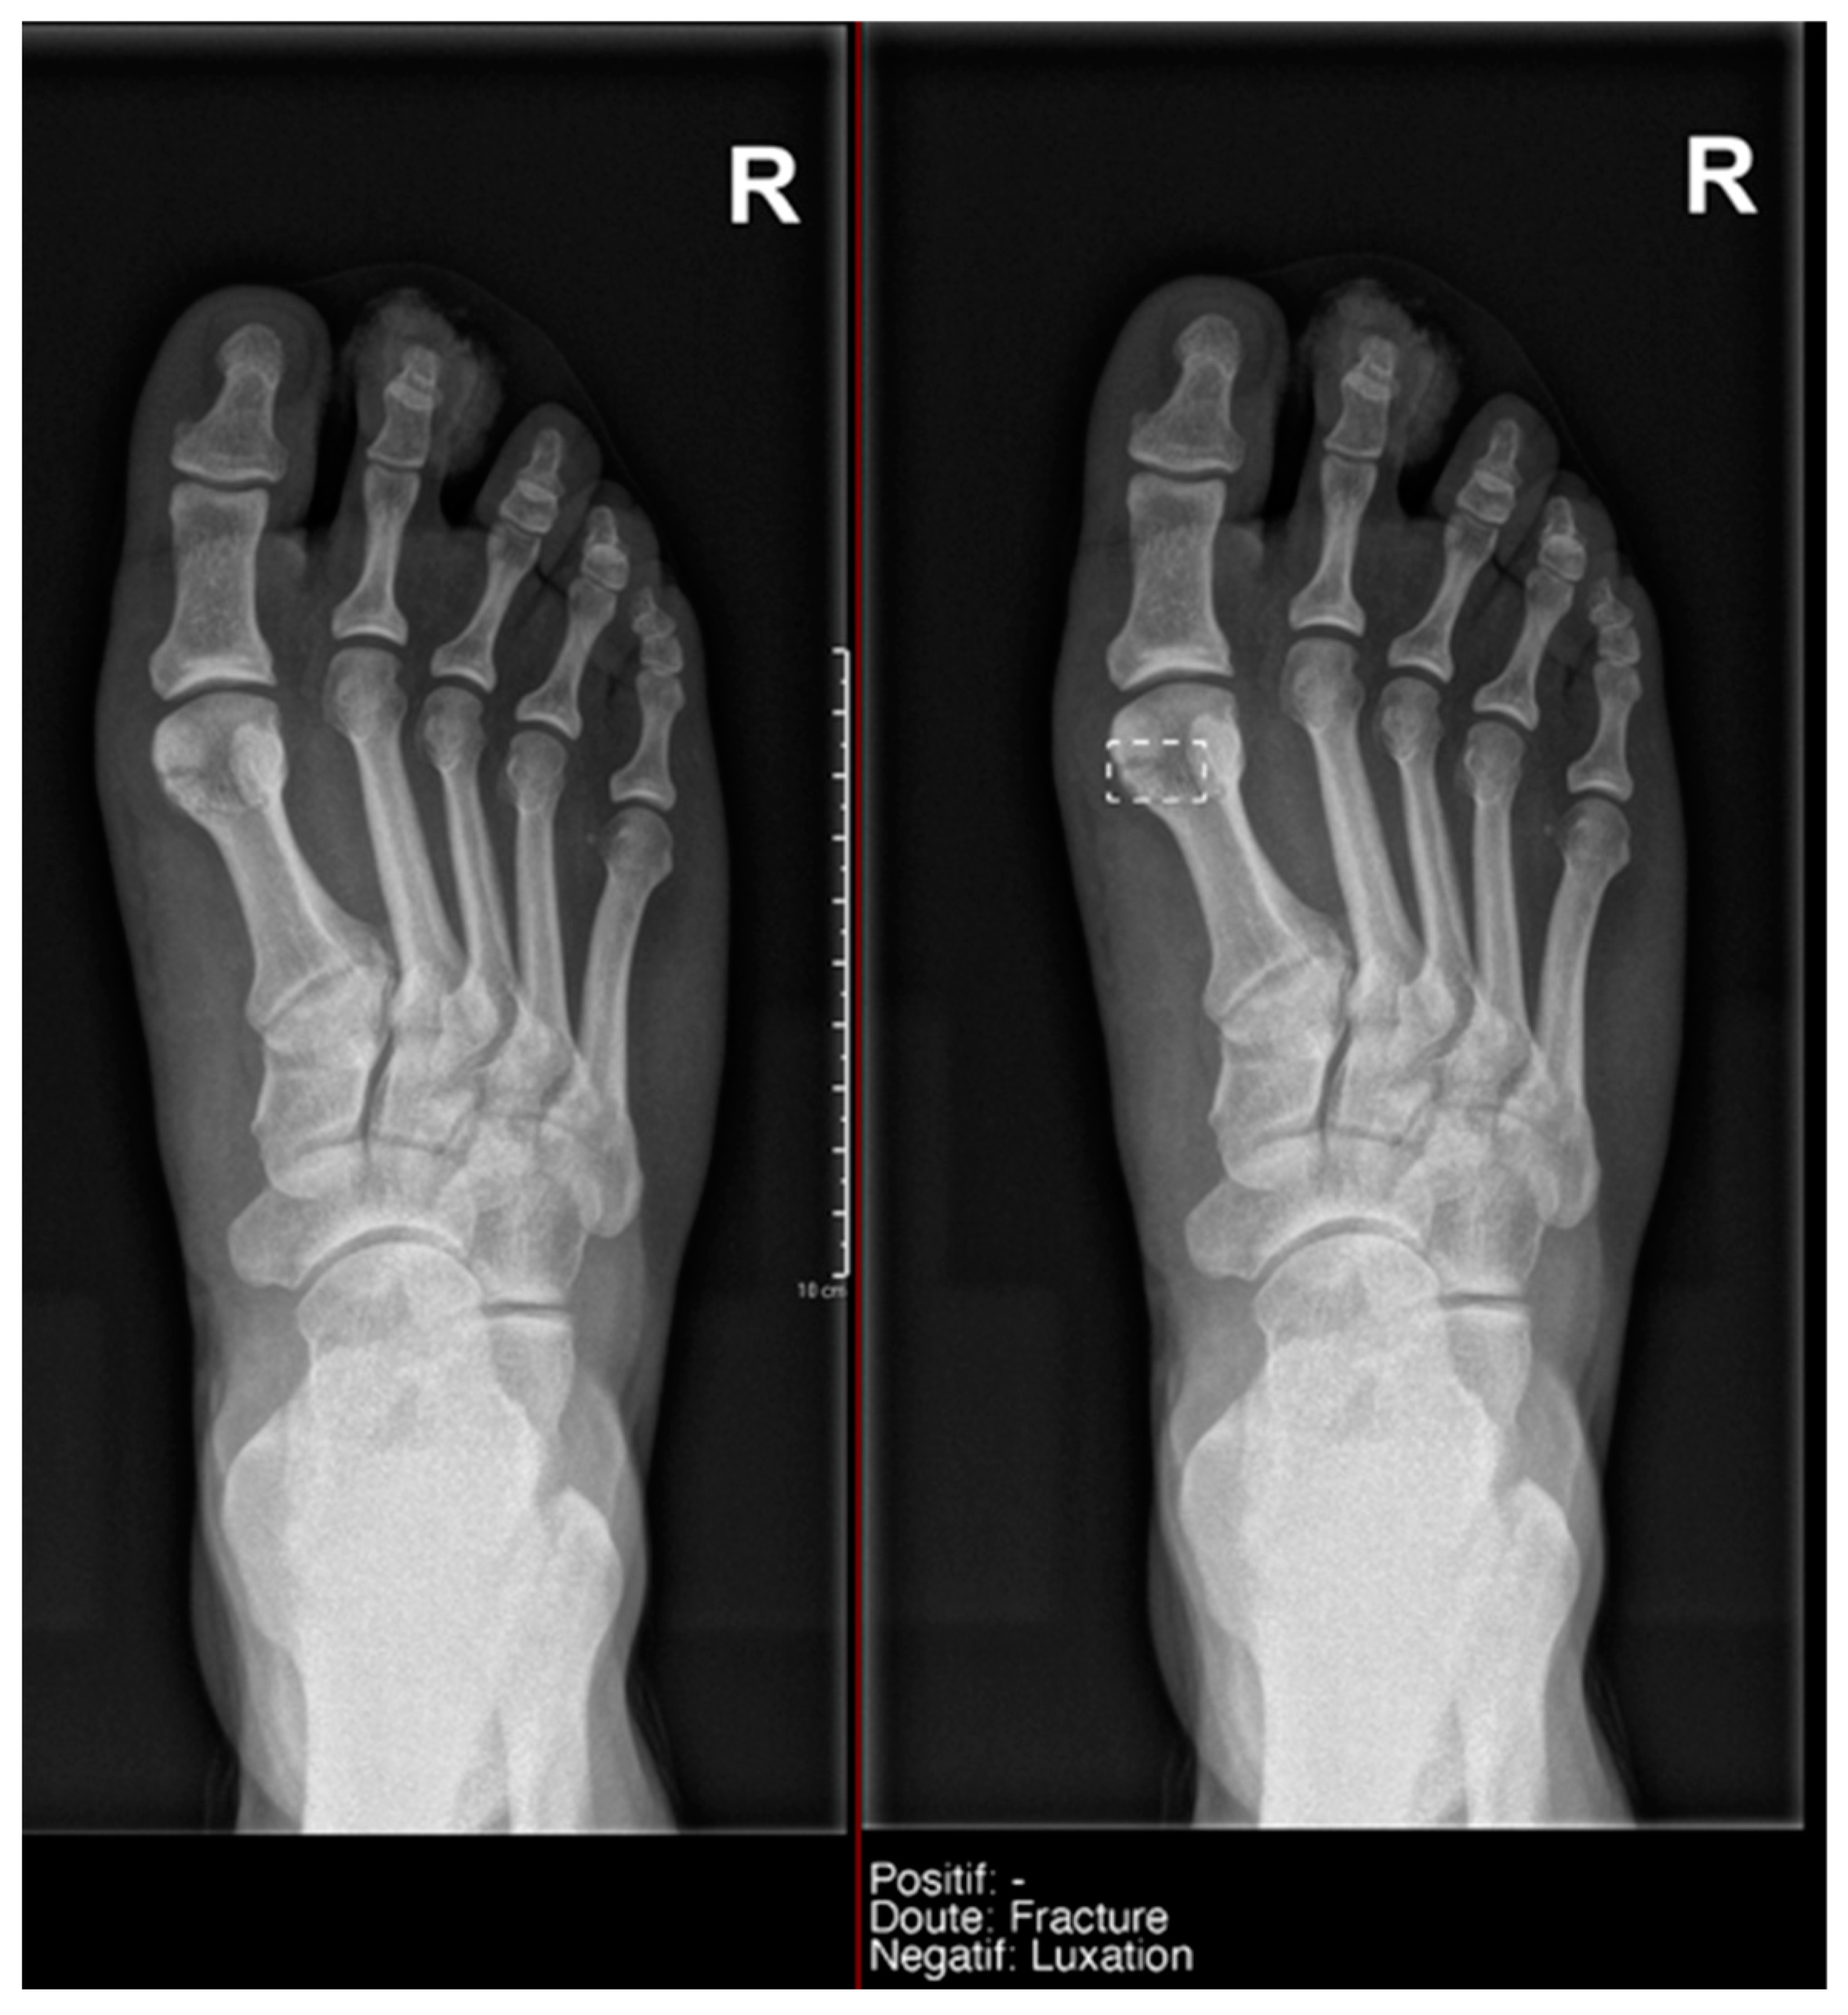

What we found particularly noteworthy was that in the overall group, we recorded 12 doubts by the resident, and 50% of them were confirmed by the gold standard. Milvue provided a higher number of doubtful cases—58 cases—but the proportion of positive cases was lower (only 25.9%) (Figure 7).

Figure 7.

Example of a doubtful fracture marked with a dashed-line box on the AP knee radiograph, which corresponded to a Pellegrini–Stieda lesion.

- Ankle and foot: On six occasions, Milvue marked the fracture variable as doubtful in cases with a bipartite medial sesamoid (two patients), an accessory sesamoid at the base of the 5th metatarsal, synphalangism, os peroneum, and os naviculare. (Figure 8).

Figure 8. Example of an anatomical variant (bipartite hallux sesamoid), which was recorded as doubt fracture by AI and as negative by the radiology resident. - Hand: Milvue marked the fracture variable as doubtful in the case of multiple accessory ossicles.